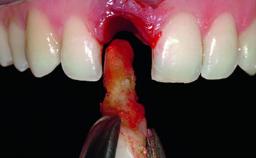

Replacement of a Compromised Upper Right Central Incisor: Hard- and Soft-tissue Augmentation, Late Placement of an RC Bone Level Implant

A 36-year-old male patient with a compromised maxillary central incisor was referred by his general dentist for consultation. The patient’s chief complaints were the gradual debonding of a temporary crown on the right central incisor and unsatisfactory esthetics due to an increasing diastema between the right central and lateral incisors. The patient reported a traumatic event some years previously, when a crown had been placed after root-canal treatment. The referring dentist wanted to provide a new crown restoration, but was concerned about the condition of the residual root. Anamnesis was negative for any other dental or periodontal pathology in the remaining dentition. The patient reported taking no medications: He was a smoker (10 to 15 cigs/day) and had realistic esthetic expectations.

Bone Augmentation Horizontal|Simultaneous|Staged

Augmentation Materials Xenogenous|Membrane

Placement Protocol Early or late implant placement

Bone Volume Deficient horizontally, requiring prior grafting